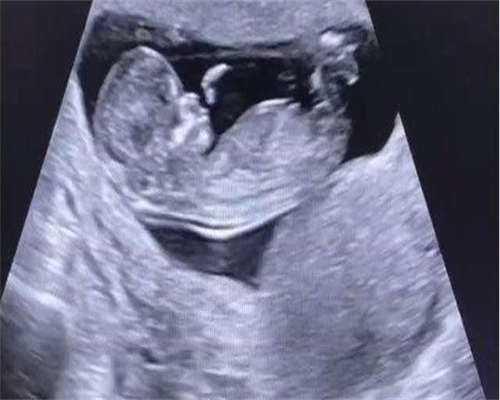

3 试管婴儿健康风险高

尽管统计显示,试管婴儿与自然妊娠分娩的婴儿出生缺陷率没有显著差异,但辅助生殖技术产生的群体与自然生产的群体还是有一定差异,试管婴儿及通过其他人工协助技术受孕的婴儿出生时出现早产、体重过轻等问题及患病率、死亡率均比自然受孕的婴儿要高。对于母亲来说,多胎妊娠也更危险,会增加妊娠高血压和糖尿病的发生。